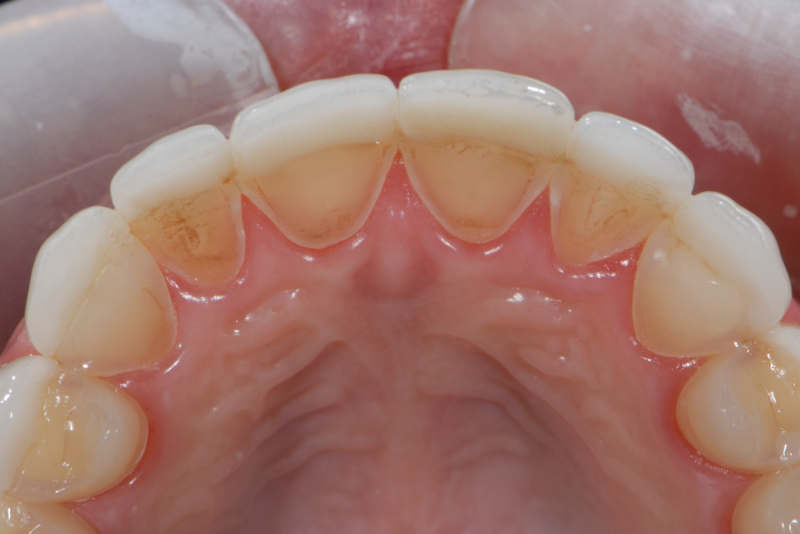

Self-induced vomiting increases the risk of dental erosion by a factor of 5.5 compared to healthy controls. These intrinsic erosion lesions are most commonly found on the palatal surfaces of the maxillary teeth, followed by the occlusal and then the buccal surfaces (Figs. 1–5).